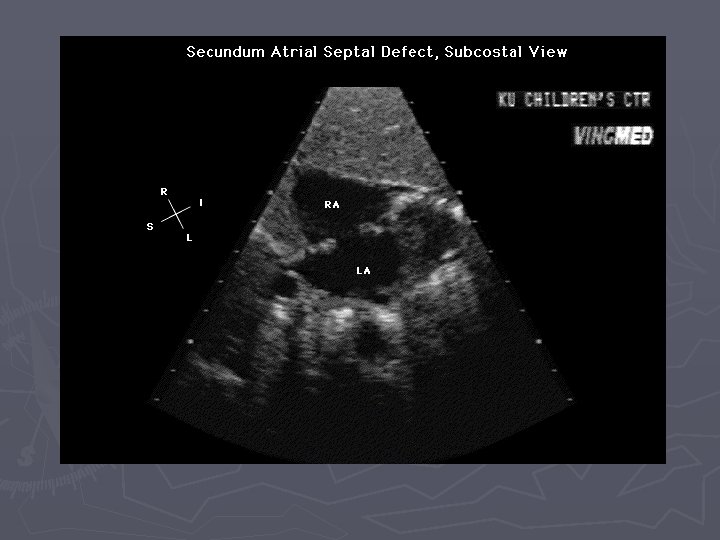

Imaging ASD ► Primary diagnosis made by echocardiography in infants and children ► MRI is emerging as accurate alternative for depiction of function, flow, and anatomy in older patients

Findings ► XR – small to moderate defects have normal radiographs ► XR - large defects have cardiomegaly with the main PA normal or enlarged, with shunt vascularity, later on PA and RV enlarge ► CTA – defect in atrial septum, enlargement of RA, RV and PA ► MR – can quantify shunt volume on volumetric cine MR or velocity encoded cine MR

Findings ► Echo – “drop out” in atrial septum best seen on apical 4 chamber view ► Angio – can also be used for transcatheter percutaneous treatment